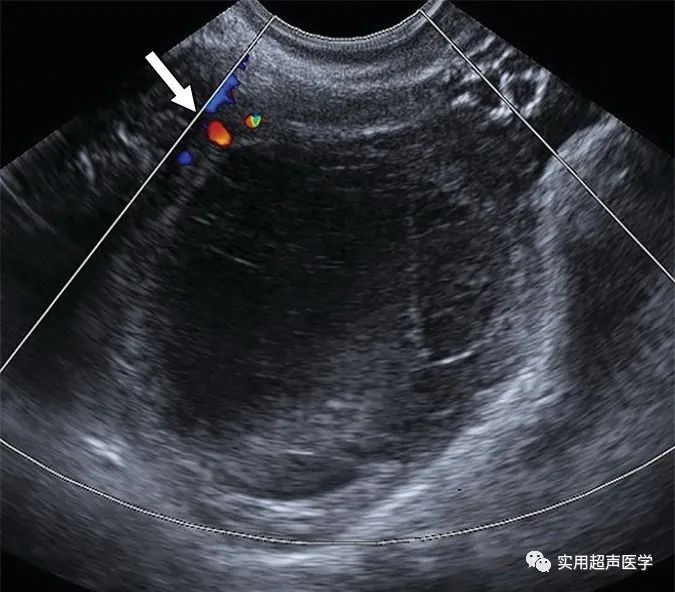

28岁女性,因出血性囊肿而疼痛。彩色多普勒超声图像显示卵巢实质周围血流(箭头),可确保进行充分的色流评估,增加诊断信心。当进行彩色多普勒成像时,必须在盒子内可视化一些颜色,以确保进行充分的技术评估。